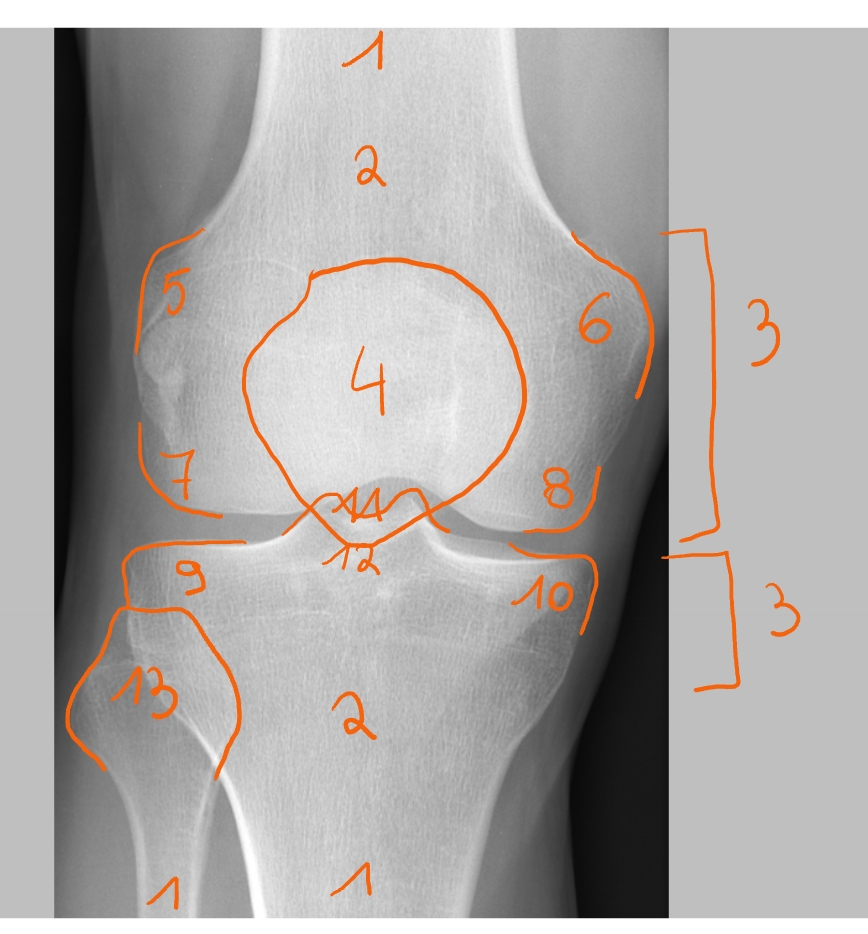

diafyse

metafyse

gedeelte waar het bot verbreedt

epifyse

patella

epicondylus lateralis

epicondylus medialis

condylus lateralis femoris

condylus medialis femoris

condylus lateralis tibiae

condylus medialis tibiae

spina intercondylaris

daarop hechten de kruisbanden aan

area intercondylaris

caput fibula

→ rechterknie